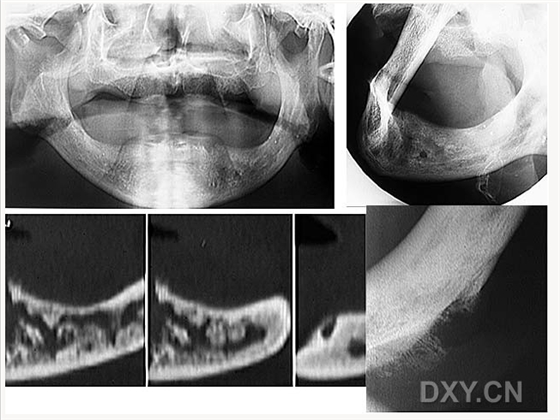

成釉細(xì)胞瘤